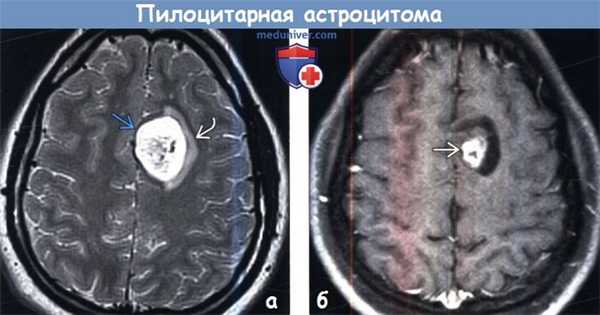

(а) МРТ, Т2-ВИ, аксиальный срез: у девушки 19 лет в лобной доле определяется гетерогенно гиперинтенсивное образование с умеренным перифокальным отеком.

(б) МРТ, постконтрастное Т1-ВИ, аксиальный срез: у той же пациентки определяется контрастирование центральной части и кистозного компонента опухоли.

Пилоцитарные астроцитомы наиболее часто локализуются в задней черепной ямке (60%) и зрительном нерве/хиазме (25-30%).

В супратенториальных отделах головного мозга пилоцитарная астроцитома (ПА) наиболее часто прилежит к III желудочку. Пилоцитарная астроцитома (ПА), локализующиеся в больших полушариях, встречаются редко.

Наличие кистозного и солидного компонентов являются типичным признаком подобных опухолей I степени злокачественности по классификации ВОЗ (grade I).